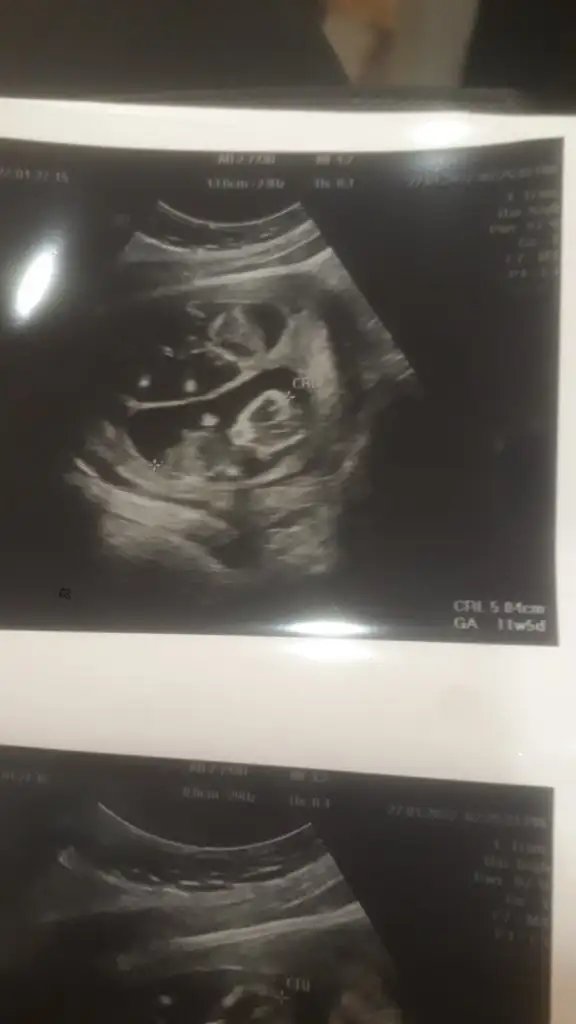

Şükür kuzum harika haber benimde hep bı hafta önde çıktı doktor hiç önemi yok dedi o fetal dna yi hatta aminosentezi bile ikili de anlattı bilgi vermek zorunda lar sanırım herkese kağıtta öle yaziodu .şükür darısı başımıza canim ya uyumasi iyi daha rahat bakmıştır yerinde durmuolar sonraKuzum anca müsait olabildim.

SAT’a göre 21+3 olmasına rağmen, USG ölçümüne göre 22+3 göründü. Dondurulmuş embriyo transferinde beklediğimiz bir şey bu, problem değil dedi.

Oyy maşallah maşallah kuzularımaGünaydın canım iyiyim çok şükür sen nasılsın nasıl gidiyor yok kuzum dr cuma günü kesin soylerim dedi cinsiyeti ama bence gördü biseyler o yüzden o kadar emin cums günü söylerim dedi bende iki kız hissediyordum ultrason görüntüsüne kadar biri icin herkes erkek oyunu kullandı diğeri kız olabilir dedi herkesbak görüntüleri atıyorum